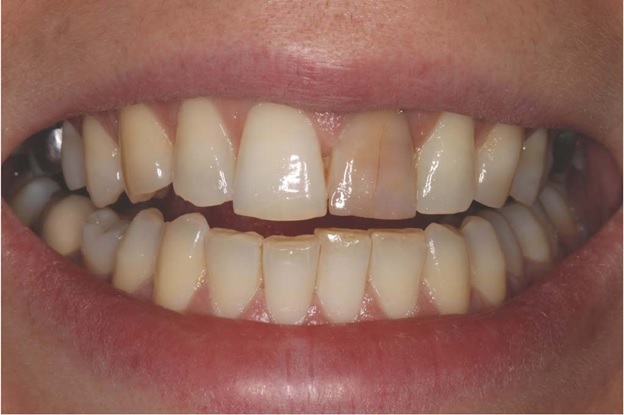

Когда мы её убрали, картина стала яснее:

-стенки зуба — розоватого оттенка;

-дно — тёмно‑коричневое;

-ткани корня-твердые

7 ) Плохая эстетика. Зуб окрашивается в розовато-коричневатый оттенок. На задних зубах это не так заметно, но передние выглядят… своеобразно. Резорцин плотно въедается в ткани, даже отбеливание не всегда работает. Часто прибегают к винирам или коронкам.